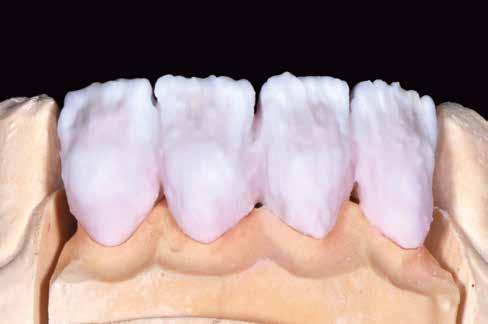

A kezelések második fázisában a pácienssel közösen non-prep/ minimálinvazív héjak készítése mellett döntöttünk (6. és 7. ábra).

Az ilyen jellegű ellátás során csupán a lehető legkisebb mennyiségű foganyag kerül eltávolításra. A minimálinvazív beavatkozás elvégzését lehetővé tevő feltételeket a fogszabályzó kezelés során alakítottuk ki. A fogazat minimálinvazív módon készített héjakkal történő ellátásához a fogaknak olyan pozícióban kell lenniük, amely lehetővé teszi az esztétikai megjelenés additív eljárások alkalmazása mellett történő optimalizálását. Azonban az ellátás során előbbiekben felsoroltakon kívül más szempontokat is figyelembe kell vennünk. Amennyiben a páciens a jelenleg látható fogszínéhez képest jelentős változást szeretne elérni, úgy sokkal vastagabb héjak készítésére van szükség, és az ezáltal megnövekedett helyigény miatt sok esetben nincs lehetőség kizárólag additív eljárások alkalmazására (8. ábra). Mivel a cikkben bemutatásra kerülő eset ellátása során a fogazat helyzeti rendellenességei az előzetes orthodonciai kezelés keretei között korrekcióra kerültek, ezért lehetőségünk adódott a restauratív fázis minimálinvazív módon történő elvégzésére. Az általunk alkalmazott terápia hátrányai között szerepelt, hogy az elvégzett beavatkozások időigénye miatt a tervezett végeredményt csupán viszonylag hosszú idő után tudtuk elérni.